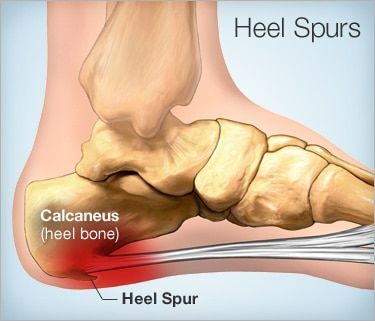

Topuk dikeni topuğun alt kısmında oluşan ve yüksek oranda kalsiyum içeren kemik uzantısıdır. Ayak röntgen grafisinde (X-ray) adeta büyük bir dikeni andıran görüntüden dolayı da “Topuk Dikeni” olarak bilinir.

Topuk dikenleri çoğu zaman ağrısız sızısız olsa da bazen çok ciddi ve dayanılamaz ağrılara neden olabilir. Bu ağrıların nedeni aslında topuktaki dikene eşlik eden ve topuk kemiğini (heel) ayak tabanına bağlayan zarın ve bağdokusunun iltihaplanmasından kaynaklanır (plantar fasciitis)

- ayak tabanı bağdokusunun gerilmesi (plantar fascia),